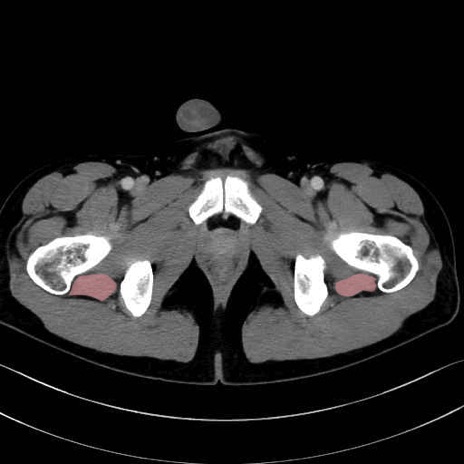

大腿方形筋(Quadratus femoris muscle)のCT画像の解剖

4. 深層外旋六筋(股関節の深部)

大腿方形筋 (Quadratus femoris)